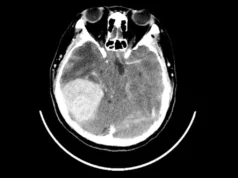

Situația a atins cote suprarealiste deoarece Fairchild era, în acel moment, însărcinată cu al treilea copil al ei și al lui Townsend. Pentru a elucida misterul, instanța a ordonat ca un funcționar oficial să fie prezent fizic în sala de nașteri pentru a asista la venirea pe lume a bebelușului. Rezultatul testului ADN efectuat pe nou-născut a fost la fel de halucinant: copilul se potrivea genetic cu tatăl său, Townsend, dar nu avea nicio legătură genetică cu Lydia Fairchild.

Răspunsul a fost validat prin runde suplimentare de teste. Eșantioanele prelevate din colul uterin al lui Fairchild au scos la iveală o linie genetică ce se potrivea perfect cu cea a copiilor ei. În schimb, ADN-ul colectat prin metode obișnuite – din obraz, păr, piele și sânge – a produs un profil genetic cu totul diferit. Pentru o siguranță absolută, mama lui Fairchild a furnizat și ea probe ADN, care au dovedit fără urmă de îndoială că este bunica maternă a copiilor.